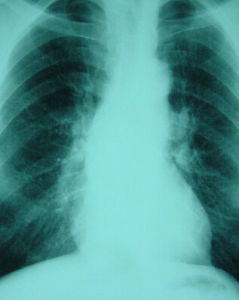

結核性鈣化X線表現(圖1):